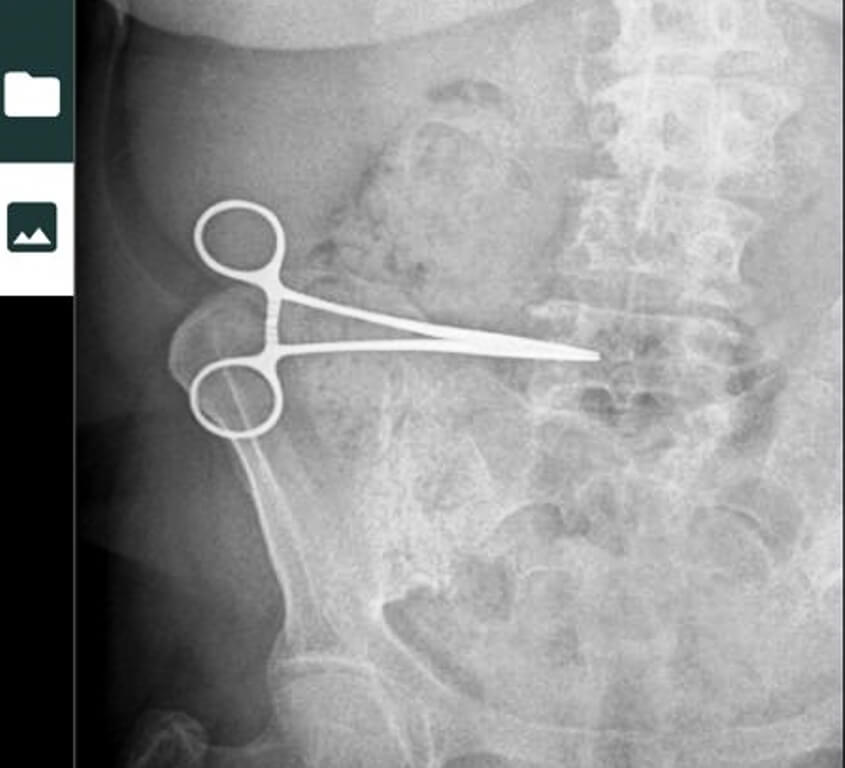

Yaklaşık 2 ay bu sorunu yaşayan kadın, Söke Devlet Hastanesine giderek çektirdiği röntgenle karnında makas olduğunu öğrendi.

Burada aldığı röntgeni Aydın’daki özel bir hastaneye götüren kadının karnındaki makas, operasyonla çıkarıldı.